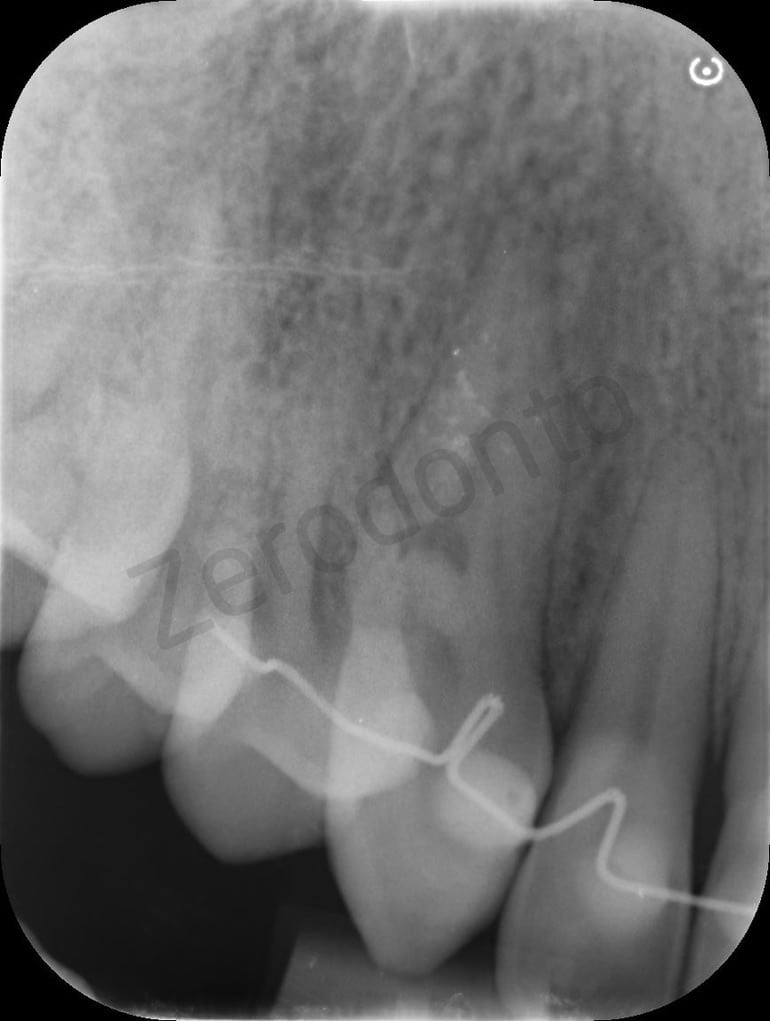

Initial situation

RX

Probing resorption

4mm lesion